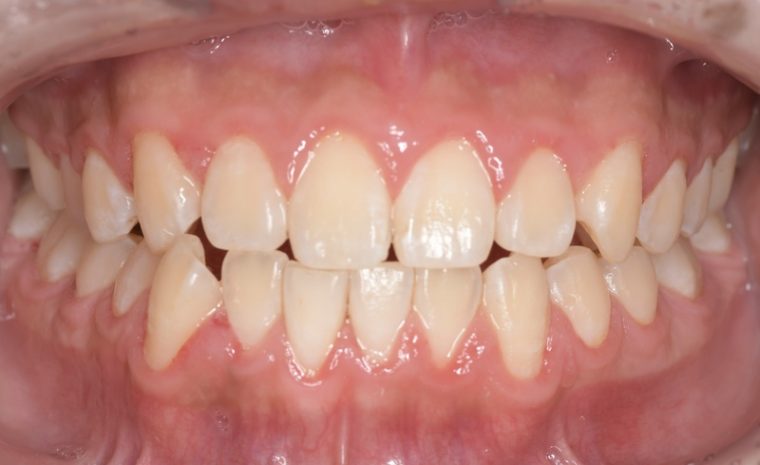

CASE 3

Before

After

基本情報

| 年齢・性別 | 30代・女性 |

| 主訴 | 定期検診 |

| 治療内容 | PMTC |

| 治療期間 | 60分 |

| 治療費 | 5,750円 |

| リスク・副作用 | しみる可能性があります。 |

| 治療方針 | PMTCでステインの除去。 |

| 担当者所見 | ステインが付きやすいため、3カ月毎の定期検診で除去する。 |